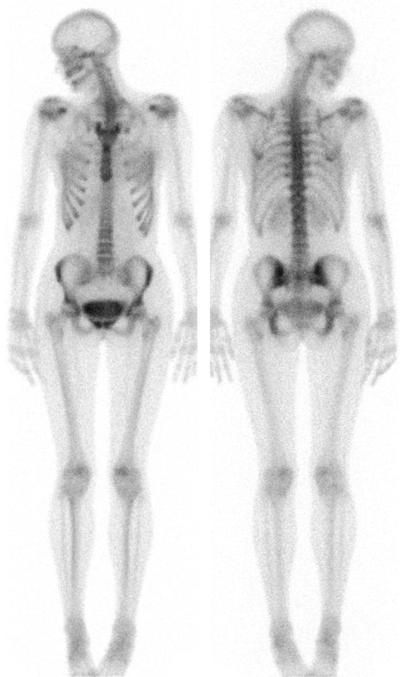

Остеосцинтиграфия – методика раннего выявления метастатического процесса в костной ткани при онкологических заболеваниях.

Ответ прост: Метастазы могут локализироваться в любой части костной системы (20% - конечности, 80% - позвоночник, ребра, грудина, череп, таз).

Остеосцинтиграфия – это радиоизотопное исследование в основе которого лежит в/в введение радиоактивного вещества (радиофармпрепарата) который накапливается в костной ткани.

По мере его накопления и распределения в скелете можно диагностировать участки повышенной концентрации - “горячий очаг” – признак усиленного остеобразования.

Реже выявляется “холодные очаги” – при склеротических и литических изменениях в костной ткани.